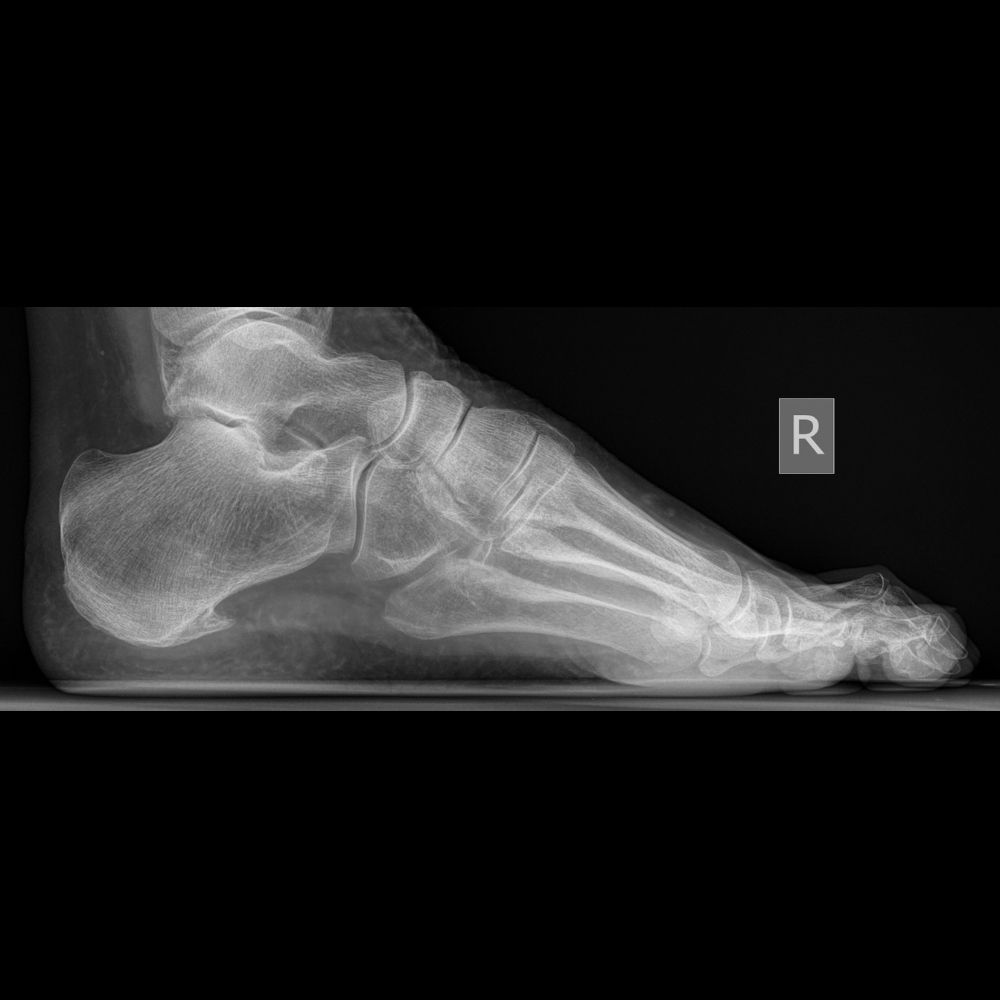

Flat Foot in a 16 year old girl with Cerebral Palsy